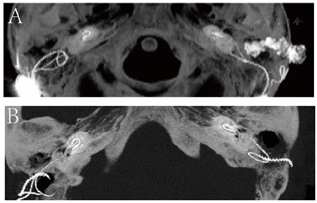

颞骨高分辨率CT检查:左外耳道内可见高密度电极导线影,耳蜗内电极已大部分脱出于蜗外,仅电极尖端部分留存于耳蜗底周,乳突腔内见少量软组织影(图2)。左侧中耳乳突炎。右侧外耳道及鼓室腔干净。

耳内镜下左外耳道内可见脓性分泌物,清理后见人工耳蜗电极导线自外耳道后壁突入外耳道内,鼓膜未见穿孔。右侧鼓膜完整,标志清楚。纯音测听检查:双侧极重度感音神经性聋。颞骨高分辨率CT检查示左外耳道内可见高密度电极导线影,耳蜗内电极已大部分脱出于蜗外,仅电极尖端部分留存于耳蜗底周。左侧中耳乳突炎。右侧外耳道及鼓室腔干净。